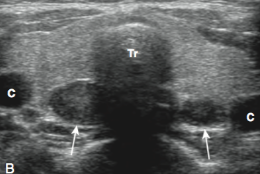

• *Asymmetrically enlarged parathyroid glands**

• Difficult to differentiate sonographically*